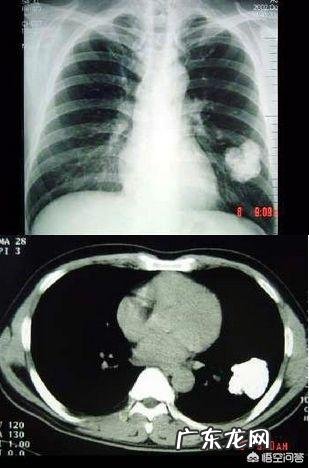

我是小影大夫 , 一名放射科医师 。每天都书写很多关于肺结核的报告 。肺结核钙化 , 这是好事 , 说明这个部位的结核已经愈合了 。结核的治疗 , 如果X胸片或者CT检查 , 出现了钙化或者纤维条索 , 都说明结核在逐渐的好转 , 应该高兴 。不仅是结核 , 很多肺部感染或者慢性炎症 , 出现钙化 , 都是好转的征象 。

得了肺结核的朋友 , 经过抗结核治疗 , 复查X线或者CT检查 。影像科医生会看片子 , 看病灶有没有吸收 , 有没有出现纤维条索或者钙化 , 如果趋向于纤维改变 , 或者已经出现了钙化 , 报告上都会有写的 。做完检查 , 拿到报告后 , 如果看到纤维条索 , 或者钙化的字眼 , 说明结核已经趋向于好转、治愈 , 看到这个 , 应该高兴 。

很多朋友得了结核 , 治疗过 , 去医院体检 , 影像科医生也会看的出来 , 因为结核的治愈会残留下纤维条索和钙化 , 这时候影像科医生会报陈旧灶肺结核 。陈旧就代表已经好了 , 残留的瘢痕 , 没有传染性 。但是陈旧性结核并不是不用管了 , 有少数人会在瘢痕的基础上长癌 , 就是所谓的瘢痕癌 , 很容易漏诊为单纯性的陈旧性肺结核 。